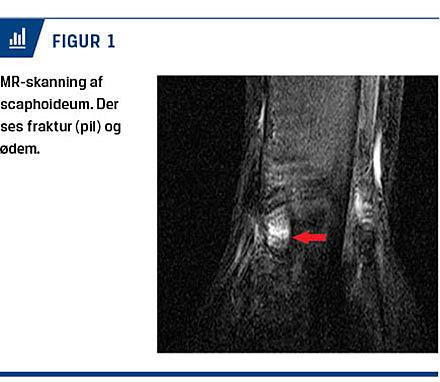

Trepunktsømheden blev genfundet ved den ambulante kontrol, men røntgenbillederne viste stadig ikke ossøs skade. I henhold til afdelingens instruks blev der bestilt subakut MR-skanning, som blev foretaget to dage senere og viste tværgående fraktur centralt i

scaphoideum og udtalt knoglemarvsødem (Figur 1). Klinisk var patienten stadig øm. Der blev anlagt en X-lite-gips dorsalt med bandagering i otte uger efter